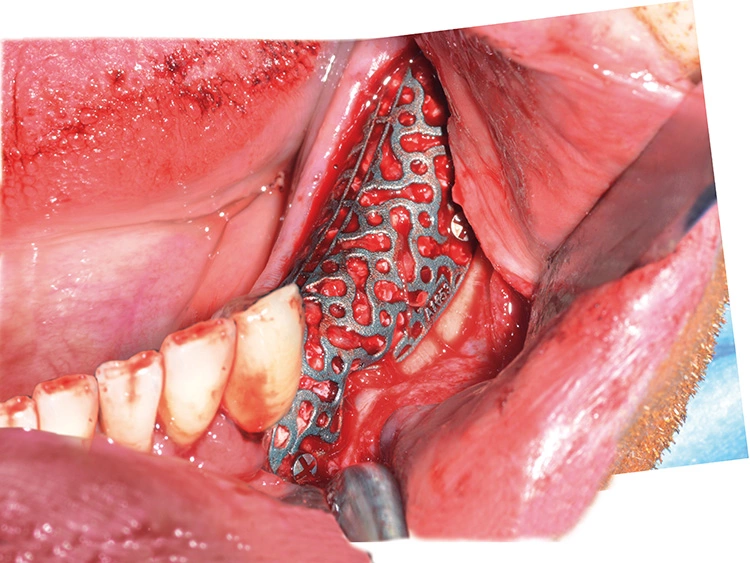

Präoperativ wurde im Sinne eines Backward Planning erst die spätere Implantatposition und in Kenntnis dieser, die Ausdehnung des Titangitters festgelegt. Hierbei wurde festgestellt, dass sich zum einen das Foramen mentale direkt im Augmentations- und Implantationsbereich befindet und zum anderen der Verlauf des Nervus alveolaris inferior, trotz Augmentation, nur relativ kurze Implantate zulassen wird.

Bei der digitalen Planung des Gitters wurde dieser Aspekt besonders berücksichtigt und zudem auf die Lage des Foramen mentale speziell geachtet. Das Gitter wurde im Austrittsbereich ausgespart, um eine Traumatisierung zu vermeiden (Abb. 4-19).

Augmentation

Trotz der schlechten, hart- und weichgewebigen Grundvoraussetzungen konnte der Kieferkamm zufriedenstellend rekonstruiert werden. Die Augmentation des kombinierten, horizontalen und vertikalen Defekts mit Yxoss CBR®, Geistlich Bio-Oss®, Geistlich Bio-Gide®, autologem Knochen und PRF ermöglichte die Implantation mit hoher Primärstabilität in den rekonstruierten Bereich.